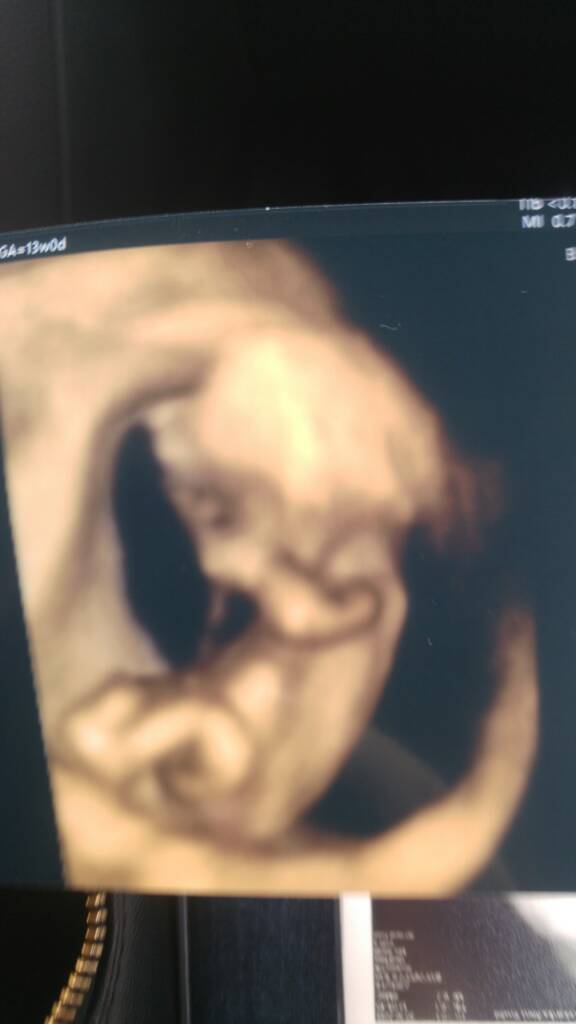

Ja siedze w kolejce do lekarza... Niestety kolejka dluga, wiec troche to potrwa. Ale mam nerwy [emoji50] a za tydzien na prenatalnych to dopiero bedzie kumulacja [emoji38]